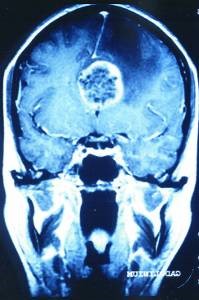

Für uns stellt diese zufällig gemachte Kernspintomographie einen wissenschaftlichen „Glücksfall“ dar, weil uns Kernspinaufnahmen, die nach solch langer Konfliktdauer in der gerade beginnenden Heilungsphase zufällig genau im „richtigen Moment“ gemacht worden sind, ein außergewöhnlich gut sichtbares Phänomen demonstrieren (mit Kontrast links, ohne rechts):

Wir sehen im Inneren des gerade in Lösung gehenden großen Hamerschen Herd (HH) noch die alten Schießscheibenringe, die nur noch kurz so gut zu sehen sind, weil sie dann im Oedem verschwimmen.

Normalerweise können wir mit dem Kernspin-Tomogramm Schießscheibenringe des HH erst nach 2 bis 3 Jahren Konfliktdauer erkennen. Und dann färben sie sich ja auch nicht mit Kontrastmittel an.

Hier aber hat der Radiologe zufällig den richtigen Tag erwischt und zufällig auch die richtige Aufnahmetechnik, mit Kontrastmittel.

Die Schießscheibenringe tauchen noch einmal wieder auf und färben sich in der pcl-Phase weiß an, um dann meist im Oedem zu verschwimmen.

Auf der rechten Aufnahme ohne Kontrastmittel ist praktisch kein Ring zu sehen.